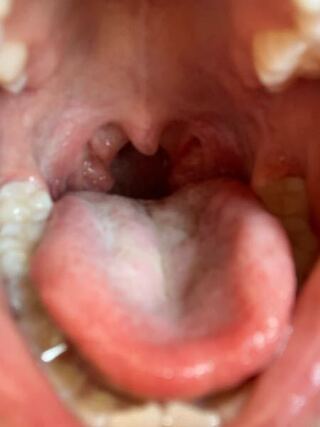

子供 7歳 ののどなんですが 扁桃腺大きいですか 今まで耳鼻 Yahoo 知恵袋

子供の喉です 扁桃腺が正常の人よりも大きい気がします Yahoo 知恵袋